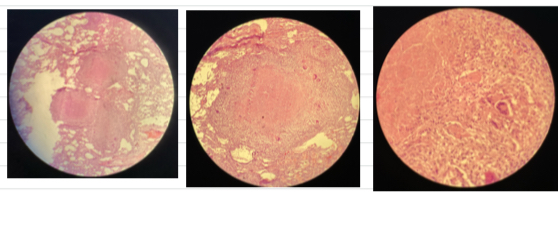

Pulmonary tuberculosis

- central necrosis surrounded by epitheloid cells w/ giant cells btw

- infiltrates of lymphocytes, plasma, fibrosis

Actinomycosis => Gram+ filamentous anaerobicrods

- accumulation of bacteria

- pyogranulomas separated w/ fibrous CT

- basophilic stained masses in centre .. surrounded with clubbed corona (eosinophilic material) then neutrophils then macrophages